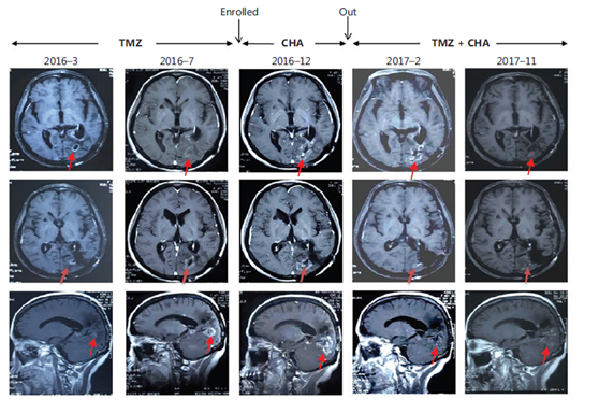

治療惡性腦膠質(zhì)瘤Ⅰ期臨床研究特殊病例分析:注射用綠原酸有效延長受試者生存期,并能一定程度解除受試者對替莫唑胺的耐藥現(xiàn)象

受試者入組時替莫唑胺耐藥且疾病進展;

使用注射用綠原酸后病情得到有效控制,出組后再次使用替莫唑胺治療,MRI結(jié)果顯示替莫唑胺再次起效。

患者采用替莫唑胺與注射用綠原酸交替使用、聯(lián)合治療的方案,顱內(nèi)病灶目前已完全消失,從確診至今,生存期已超過13年。

病例圖片來源 Kang, Z. , Li, S. , Kang, X. , Deng, J. , Yang, H. , & Cheni, F. , et al. (2023). Phase Ⅰ study of chlorogenic acid injection for recurrent high-grade glioma with long-term follow-up. 癌癥生物學與醫(yī)學:英文版, 20(6), 465-476.